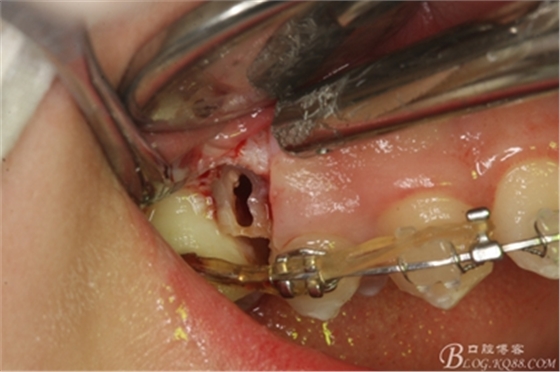

圖13. 用小球鉆去除約1mm牙槽骨,暴露15牙根面約5mm。

圖14.用小球鉆縱分15牙根